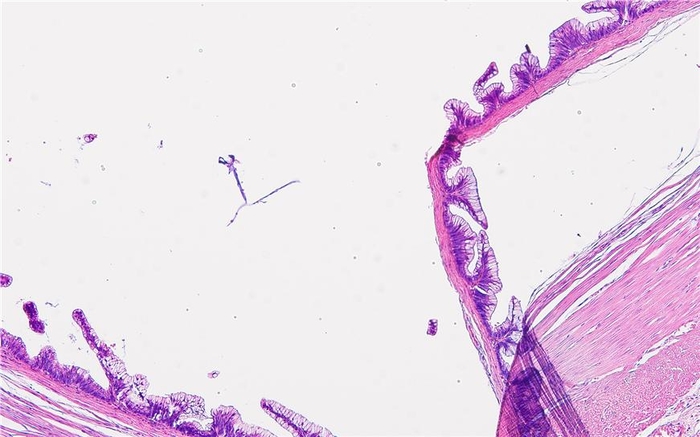

조직소견: 충수돌기에 발생한 점액종양

작품설명: 충수돌기는 일반인이 맹장이라고 부르는 장기이다. 점액종양이 발생하여 엄청난 점액을 분비하는 가운데 점액을 분비하는 세포들이 에스컬레이트 처럼 배열하였다. 이 사이를 뛰어넘는 사람이 보인다.